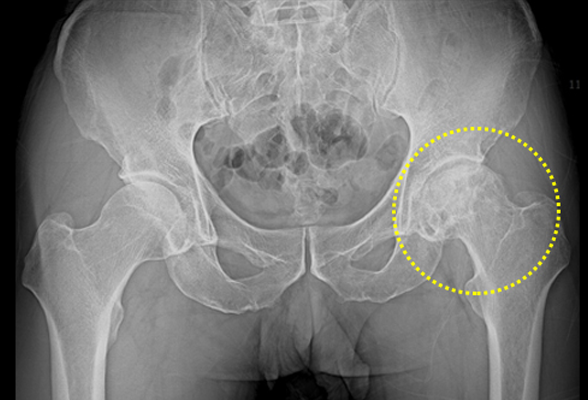

대퇴골두 무혈성 괴사

대퇴골두란 고관절의 머리 부분으로 둥근 부분을 말하는데

혈류가 차단되면 뼈 조직이 죽는 괴사증상이 나타나게 되며 이를 대퇴골두 무혈성 괴사라고 합니다.

치료법

비수술 치료 : 약물치료

수술치료 : 인공관절 치환술